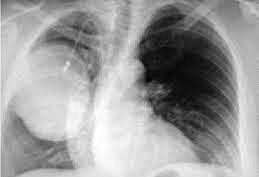

Для подтверждения диагноза проводится консультация онколога и торакального хирурга, уточняются данные анамнеза, назначаются инструментальные обследования. Заподозрить саркому легкого можно по быстрому прогрессированию опухоли у лиц молодого возраста. Ведущее значение в выявлении саркомы легких имеют лучевые методы (рентгенография, КТ легких). На рентгенограммах определяется округлая или овальная тень с неровными краями, которая чаще локализуется в периферических отделах. При динамическом контроле отмечается быстрое увеличение опухоли. КТ и МРТ легких позволяют более детально проанализировать параметры опухоли и произвести стадирование процесса.